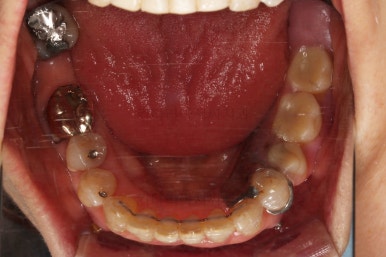

초진 시 입안의 모습입니다.

일반적인 교정을 하기에는 적합한 모습은 아니었어요.

치아는 군데군데 없고 임플란트도 있고 브릿지로 연결된 치아도 있으며 전반적인 잇몸 상태도 좋지 못했어요.

앞니가 벌어져 있고 뻗쳐 있으며 잇몸에서 쏙 빠져나와 있는 듯한 느낌이었어요.